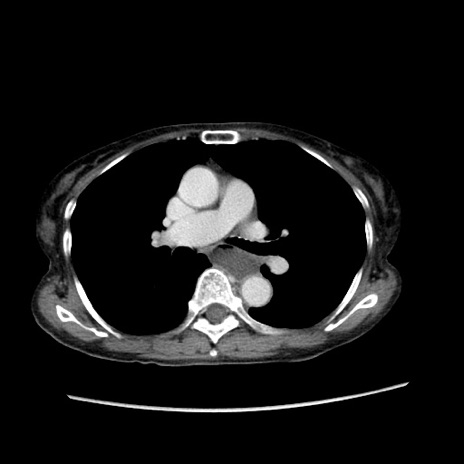

症例25(横断像)

【症例】80歳代女性

【主訴】胸のつかえ感

【現病歴】約9時間前に食後から胸のつかえた感じあり、嘔吐あり、来院。

【既往歴】胃癌(全摘)、胆摘、虫垂炎

【身体所見】心窩部に圧痛あり、反跳痛なし。

【データ】WBC 5700、CRP 0.05